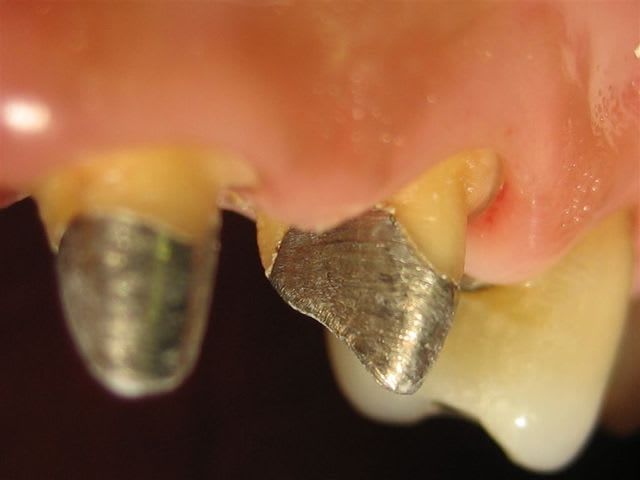

... un autre cas, mais ça ressemble toujours à ça >

Dans des teintes assez soutenues et peu translucides je trouve que la ccm avec ce type de joint rivalise bien avec les techniques plus "modernes"...